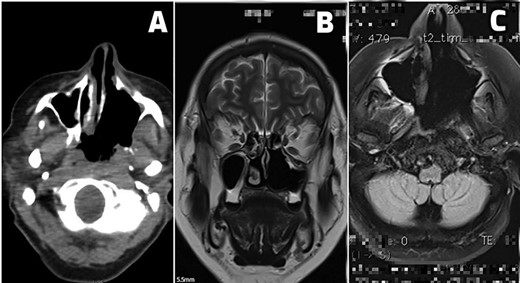

Till this day, the patient is free of local tumor recurrence and distant tumor as illustrated in Fig. 2A–C.

(A–C) Postoperative scans. (A) An early postoperative PET CT scan shows tumor margins and postoperative sinonasal cavity. (B and C) MRI scans of patients free of local tumor recurrence and distant tumor spread at 24 months (B) and 36 months (C) of regular postoperative follow-up.